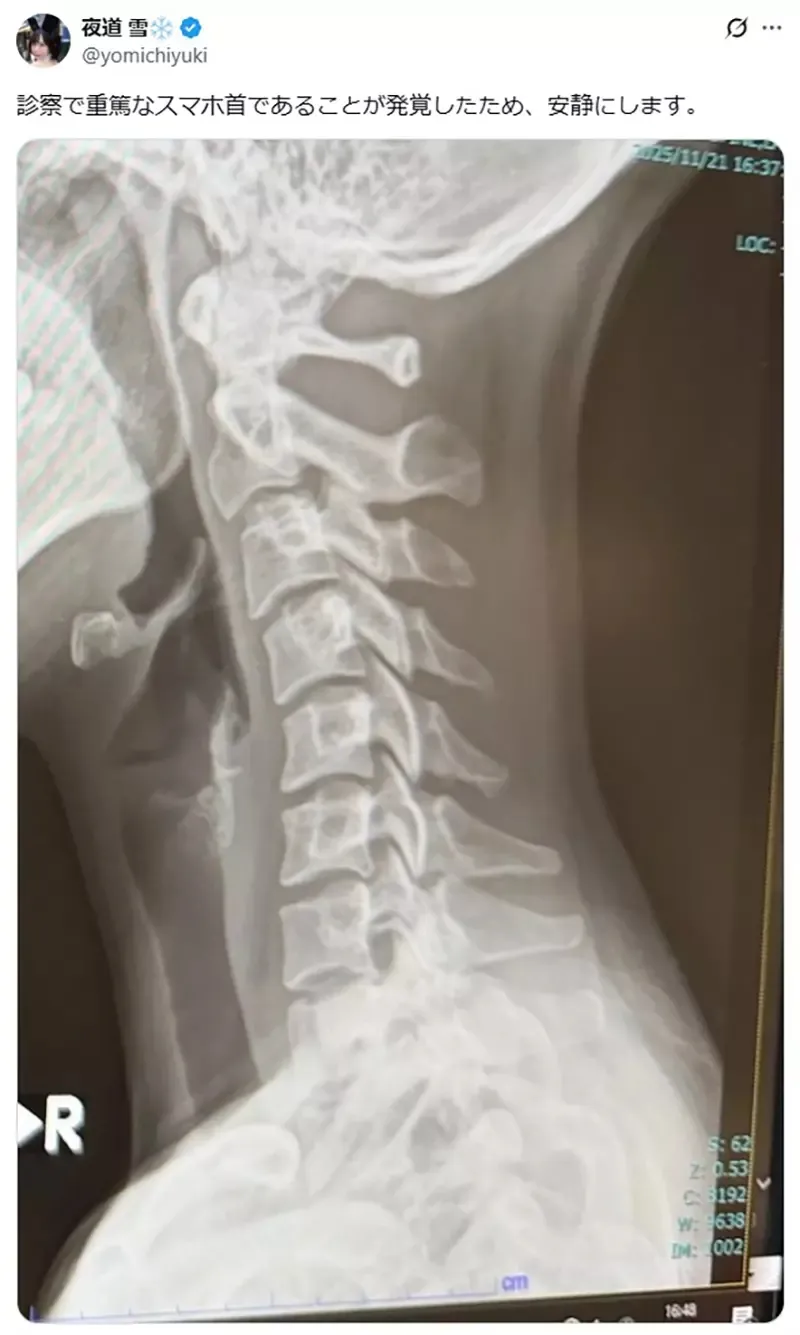

「检查发现我的脖子有严重的低头族症状,所以我会好好休养。」